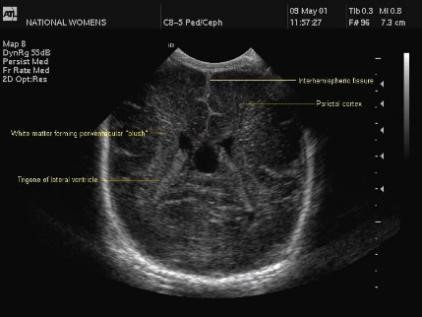

4. Trigone

This image is taken by angling further back to cut through the trigones of the two lateral ventricles. It is easy to see the choroid plexus that fills both ventricles – it is usually quite prominent in preterm infants. It is, however, difficult to differentiate between bulky choroid and choroid plexus hemorrhage. The white matter evident in the image is called "flare" or "blush" and usually appears quite bright in this plane.